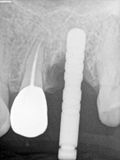

RYang - immediate 26 and apico 25

R3.jpg